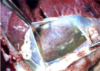

Pericardial Effusion

“Mulberry Heart Disease”

Inflammatory edema

Fibrin strands and cloudy appearance of pericardial fluid